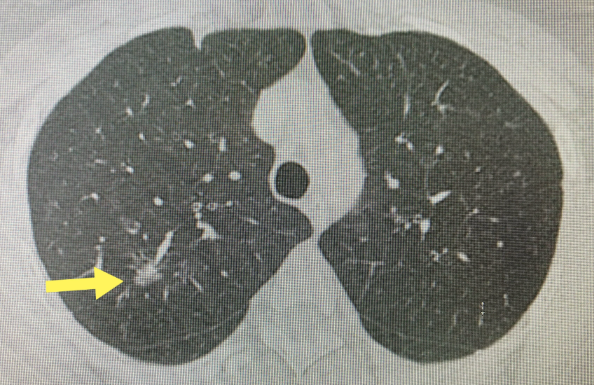

肺部结节是指肺内直径小于或等于3cm非正常的组织,可以是圆形或不规则形状的。其中直径小于1厘米的称之为小结节,直径小于3毫米的称之为微结节,而大于3厘米的我们称之为肿块。肺结节可以表现为单独一个,也可以是多个。

根据结节的密度,可以分为以下三种类型:

1、磨玻璃结节

在肺中有一些密度比较低的像磨渣样的玻璃,或者类似云雾一样的、小片状的、比较局限的结节,或者有时像一团小棉花一样的结节。就像我们的磨玻璃一样,能隐隐约约看到玻璃后面的场景,所以叫磨玻璃结节。

2、实性结节

结节的密度很高,完全不透明了,好比我们的鸡蛋黄一样,结节内部有填充物,看不到后面的肺纹理。

3、混杂型磨玻璃结节

在 CT 图像上表现为磨玻璃和实性结节的混合,就像蛋清包绕蛋黄,外周是类似于蛋清的磨玻璃成分,中间是类似于蛋黄的实性部分,既有磨玻璃阴影,又有实性成分。

部分结节在影像学上有一些特征性征象,如果我们在结节中看见钙化,或者实性结节的边缘非常光滑、边界非常清晰,这样的结节基本就是良性的。